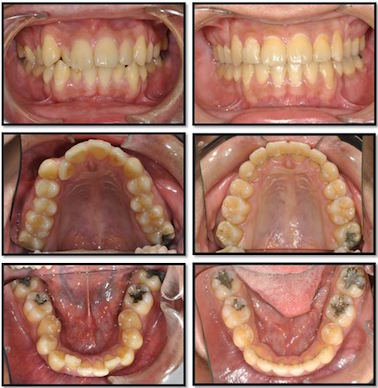

Q:矯正是否要拔牙?

拔不拔牙是矯正醫師根據患者X光片,骨頭狀態,牙齒位置,角度,方向,臉型,及牙齒雜亂的程度作全方考量,才決定是否拔牙,並非矯正一定要拔牙。